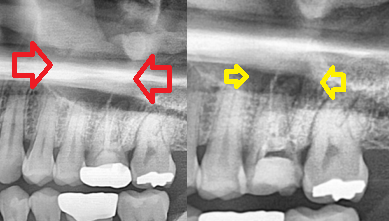

6개월 후입니다. 완전히 병소가 치유되고 건전한 뼈로 치유된 것으로 확인됩니다.(모든 임상 사진은 환자의 포괄적 동의하에 사용됩니다)오 항상 교정 치료 중인 어금니에 잇몸 농낭이 생겨 의뢰받았고 치근단 절제술로 완치된 리뷰에 대해 게시해 보았습니다. 잇몸농포, 어금니 재치료, 어금니 치근단절제술에 대해 궁금한 사항은 문의주세요 저/범치과 대표원장 김지아 * 이글과 함께 읽어보면 좋은 칼럼*<잠원동치과 미세현미경 치근단절제술 리뷰를 공개합니다>서초치과 미세현미경 치근단절제술 리뷰를 공개합니다 안녕하세요 서초치과봄치과의원 치과보존과 전문의 김지아입니다. 블로그의 모든 글은 대표원장인 제가 직접… blog.naver.com<잠원동 치과 발치 판정 전 치아 확실한 치료를 원한다면 필독>서초치과 발치 판정 전이므로 확실한 치료를 원하시면 필독 안녕하세요 서초치과봄치과의원 치과보존과 전문의 대표원장 김지아입니다. 블로그의 모든 글은 대표원장이다…blog.naver.com서초치과 발치 판정 전이므로 확실한 치료를 원하시면 필독 안녕하세요 서초치과봄치과의원 치과보존과 전문의 대표원장 김지아입니다. 블로그의 모든 글은 대표원장이다…blog.naver.com서초치과 발치 판정 전이므로 확실한 치료를 원하시면 필독 안녕하세요 서초치과봄치과의원 치과보존과 전문의 대표원장 김지아입니다. 블로그의 모든 글은 대표원장이다…blog.naver.com범치과의원 서울특별시 서초구 신반포로 177 반포쇼핑타운 3동 3층 310호범치과의원 서울특별시 서초구 신반포로 177 반포쇼핑타운 3동 3층 310호범치과의원 대표전화 02.537.6124범치과의원 대표전화 02.537.6124범치과의원 대표전화 02.537.6124